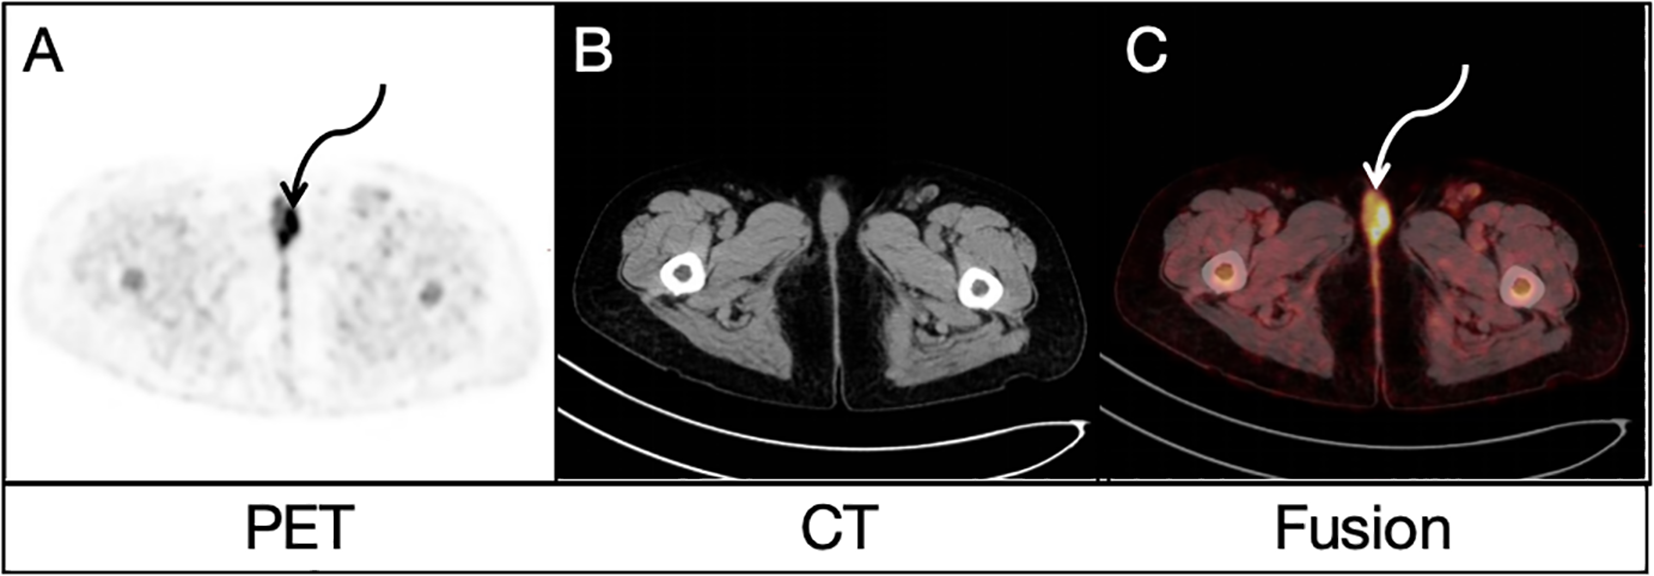

FDG uptake in many lesions in the liver, bones and lymph nodes might suggest multiple metastases, but the location of primary lesion was unclear. Due to the existence of bilateral inguinal lymph node metastases, the vulvar lesion was suspected to be the primary lesion. To further clarify the diagnosis, this patient underwent a delayed pelvic FDG PET/CT imaging at 2 h after FDG administration, and the results demonstrated multiple possible malignant lesions in the vulva (Figures 2A, C, curved arrows), with a furtherly increased SUVmax of 10.2 while no evidence of anatomical abnormality in the corresponding area on CT image (Figure 2B). A more detailed medical history was then taken. The woman had been complaining of vulvar inflammation and pain for years. The physical examination had revealed the presence of stiffness and swelling in the mons pubis, accompanied by two erythematous lesions of 1.0 cm in diameter. According to the medical history and findings of dual-time-point 18F-FDG PET/CT, vulvar carcinoma with liver, bone and lymph node metastasis was suggested.

Figure 2. Delayed pelvic FDG PET/CT findings: Both PET image (A) and PET/CT fusion image (C) demonstrated similar possible malignant lesions (curved arrows) in the vulva, with a SUVmax of 10.2 while no evidence of anatomical abnormality in the corresponding area on CT image (B).